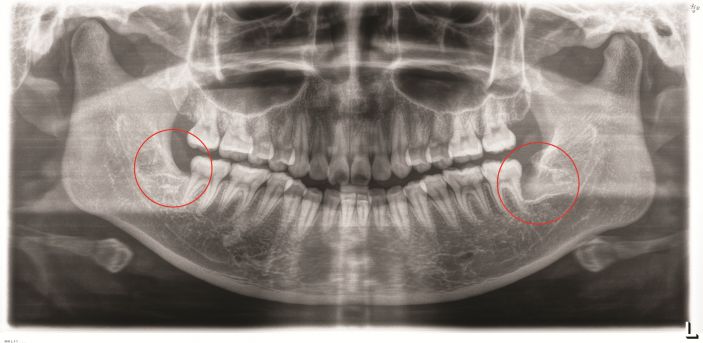

△智牙拔除後。

張主任講,微創拔智牙融合了多種先進的技術和理念,讓拔牙方式徹底告别盲目、暴力時代,具有這些優勢:1、個性化。術前通過CBCT明确患牙形态、埋伏深度及與下槽骨神經管、鄰牙的關系,分析骨阻力,設計、制定個性化的方案。2、創傷小。根據患牙特征,以減小創傷爲目的設計切口,采用超聲刀、切牙機等先進儀器設備,以小切口暴露牙冠,對患牙進行準确分割後經小切口逐一取出,告别傳統敲、鑿、劈、撬等一系列機械性操作,大幅度減少對正常組織的損傷。3、疼痛小、并發症少、恢複快。微創技術的應用,大幅減少智牙拔除的疼痛以及并發症,加快了術後的恢複。